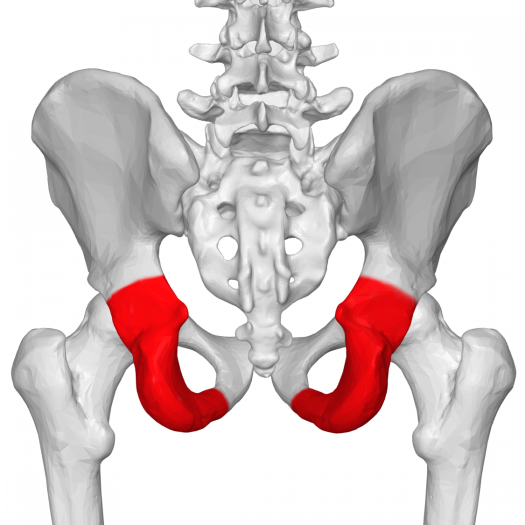

13. Name the following structure:

Explanation

The given structures, Sacrum, Ischium, Ilium, and Pubis, are the bones that make up the pelvis. The Ischium is one of the three bones that fuse together to form the hip bone or coxal bone. It is located at the lower and posterior part of the pelvis, forming the lower and back part of the hip bone.

30.  ?  The coloured structure shows

The correct answer is Buccinators. The question is asking for the name of the coloured structure shown in the image. The options provided are Zygomaticus major, Zygomaticus minor, Buccinators, and Omohyoid. Based on the options given, the correct answer is Buccinators.

Name the following structure: